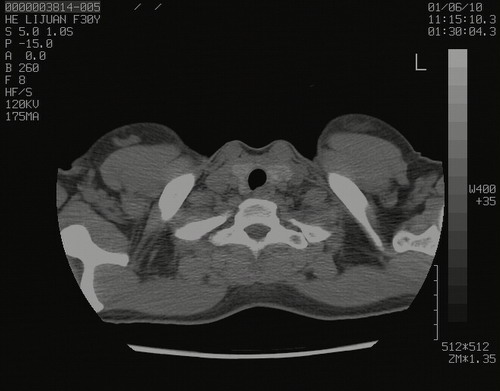

怀孕3个月时(2009-3至4月间),自述突感左侧前后胸疼痛1天,以前胸明显,随后偶感闷痛,余未见异

左肺尖脊柱旁沟肿块,境界清楚,边缘光滑,密度不均,内有多发点片状钙化,考虑良性肿瘤,骨软骨瘤或神经源性肿瘤可能,肺错构瘤不除外。

左后上纵隔见一类圆形肿块影,外侧边界清,密度不均匀,内可见点状钙化影,增强呈不均匀强化,考虑神经源性肿瘤可能。期待病理结果。